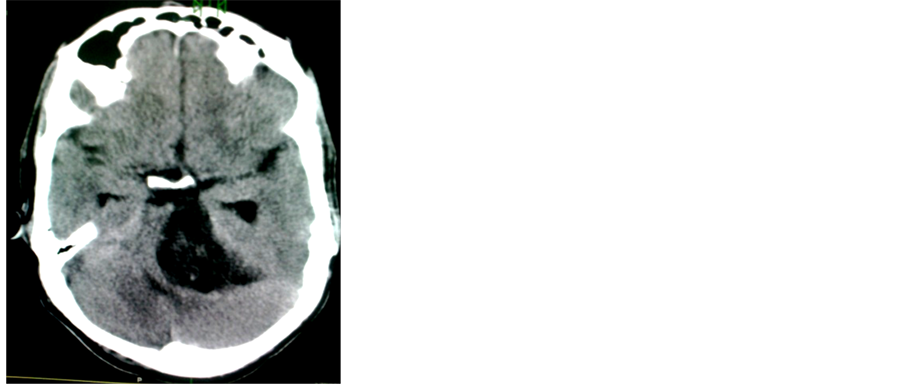

In the diagnosis of 100 cases of brain glioma the CT scan diagnoses (64 patients) (63.4%), and after the biopsy result confirmation the number of the patients decreased to (39 patients) (38.6%) as in image in Figure 1 and Figure 2.

Figure 1. The diagnosis of brain astrocytoma by CT & tissue biopsy.

Figure 2. Axial CT brain images (b) without contrast and (a) with contrast showed a mixed lesion in the left cerebellar hemisphere crossing the midline with contrast enhancement. Astrocytoma.